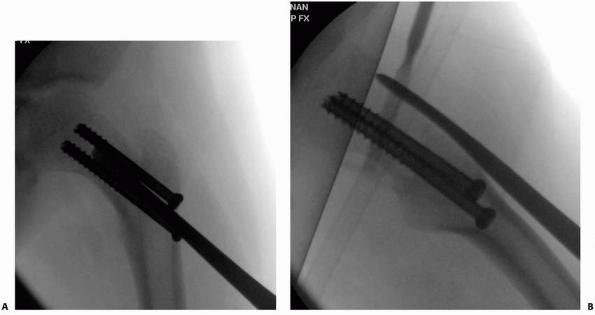

position that best aligns the bone (Fig. 21-10A,B).

intraoperative positioning (Fig. 21-10C,D).

| FIGURE 21-10 A. A 4-year-old boy fell from his window, causing a displaced type IV. B. Positioning of the hip in a spica cast is usually in hip flexion and confirmed under fluoroscopy. C. Fluoroscopic radiographs in 90 degrees of hip flexion insure anatomic correctness. D. At 1-week follow-up, radiographs were inconclusive; a CT scan assists in confirming location. |